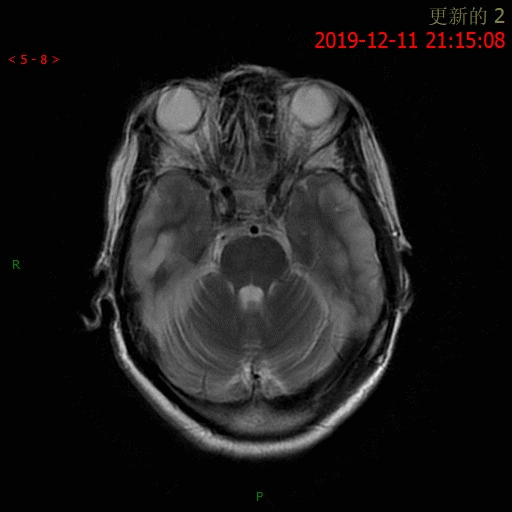

患者于 12.10 夜间烦躁不安

12.11 日 MR 平扫

患者为中年女性,临床症状不重,影像表现明显。双侧大脑半球多发病变,DWI 呈高信号,呈非对称性分布,且病灶分布呈跨血管支配区分布,DSA 为正常表现,可以排除脑梗死。短期内病灶迅速进展,MRS 可以看到明显倒置的乳酸双峰,考虑 MELAS。